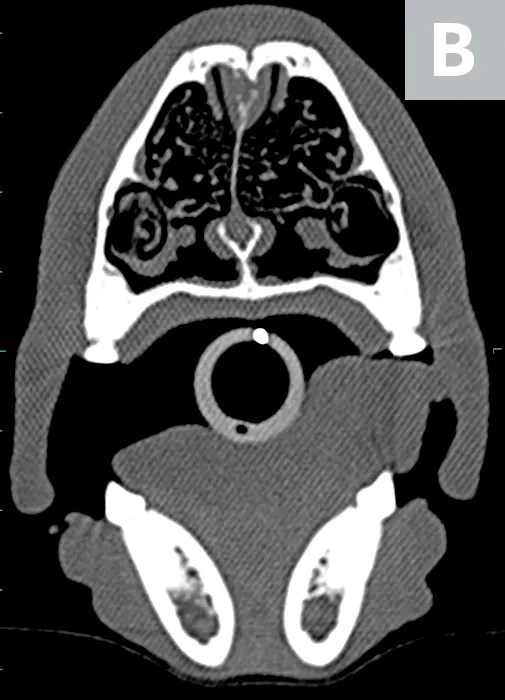

Precontrast, transverse plane CT image of the nasal passages at the level of the second premolars (A). There is an absence of complete closure of the nasal bone suture (arrows) and dilation of the most dorsal aspect of the nasal septal wall with soft tissue density (arrowhead). Precontrast, transverse plane CT image of the nasal passages at the level of the third premolars (B).